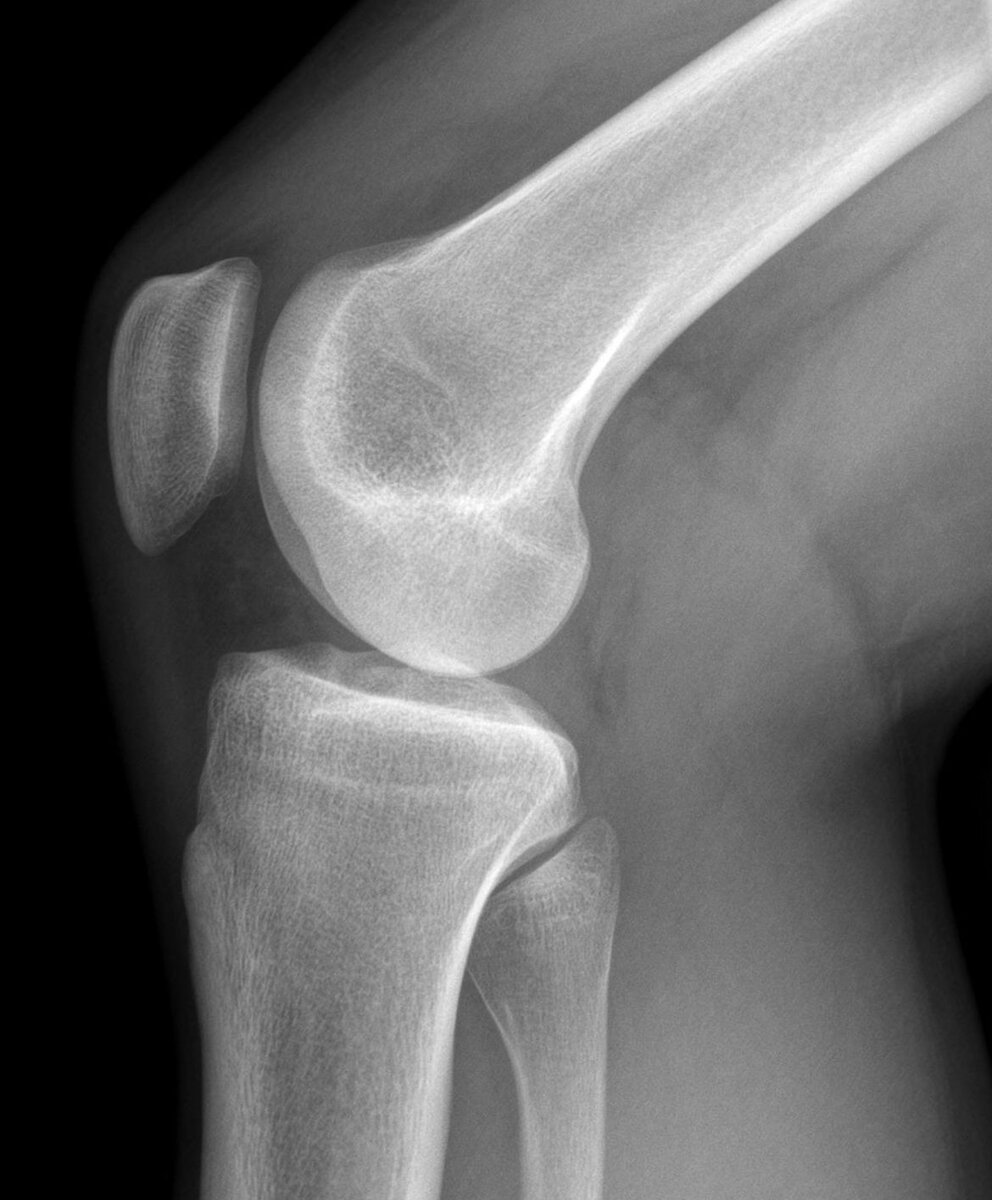

Суставы и кости